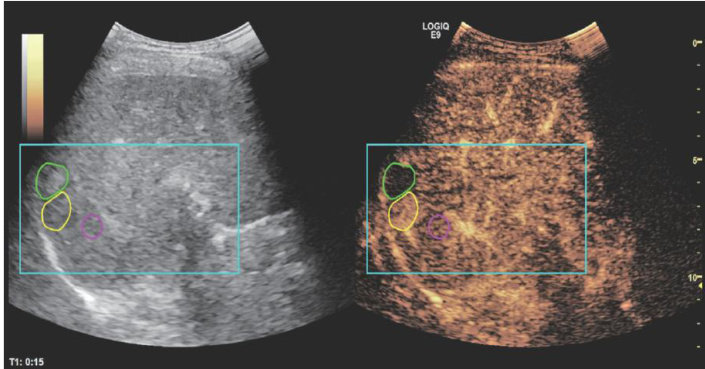

摘要目的应用经胸超声心动图(TTE)测量功能性二尖瓣反流(FMR)患者经导管二尖瓣缘对缘修复术(TEER)相关解剖参数,探讨其在评估TEER解剖适应证中的临床价值。方法选取我院经TTE初诊为FMR的患者220例,应用TTE、经食管超声心动图(TEE)分别获取患者TEER相关解剖参数,包括前瓣长度(ALL)、后瓣长度(PLL)、二尖瓣口面积(MVA)对合长度(CL)对合高度(CH)、房间隔总长(IAS),比较二者测值的差异;分别采用Pearson相关分析法和组内相关系数(ICC)分析TTE与TEE测值的相关性和一致性。以TEE分区结果为金标准,分析TTE在评估"绿区-黄区-红区"解剖适应证分类中的诊断效能。采用ICC评估TTE测量TEER相关解剖参数在观察者内及观察者间的一致性。结果TTE测量的MVA、CH、CD均高于TEE测值,差异均有统计学意义(均 P<0.05 );TTE与TEE测量的AML、PML、IAS比较差异均无统计学意义。TTE与TEE测量的ALL、PLL、MVA、CH、IAS均表现出高度相关 (r=0.864,0.833,0.955,0.896, 0.967,均 P<0.001 )及良好一致性 (ICC=0.862,0.831,0.936,0.884,0.967, 均 P<0.001 ),CL表现出中度相关 (r=0.569,P<0.001 )及较差一致性 (ICC=0.422,P<0.001) 。TTE评估FMR患者TEER三分区解剖适应证的整体准确率为 88.6% ,评估"绿区”的灵敏度、特异度、准确率分别为 98.3%.62.5%.90.5% ,评估“黄区"的灵敏度、特异度、准确率分别为 45.5% 、 96.3% 、86.6% ,评估"红区"的灵敏度、特异度、准确率分别为 73.3%.100% 98.2%。TTE测量的ALL、PLL、MVA、CL、CH、IAS在观察者内ICC分别为 0.834,0.839,0.978,0.430,0.842,0.987 (均 P<0.001 ),在观察者间ICC分别为 0.790,0.983,0.976 0.430、0.789、0.982(均 P<0.001 ),表明ALL、PLL、MVA、 CH 、IAS在观察者内及观察者间的一致性均良好,CL的一致性较差。结论TE在评估FMR患者“绿区-黄区-红区"TEER